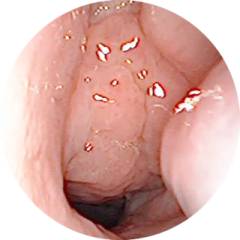

Как выглядят аденоиды на фото?

Так видит врач аденоиды во время эндоскопического исследования: